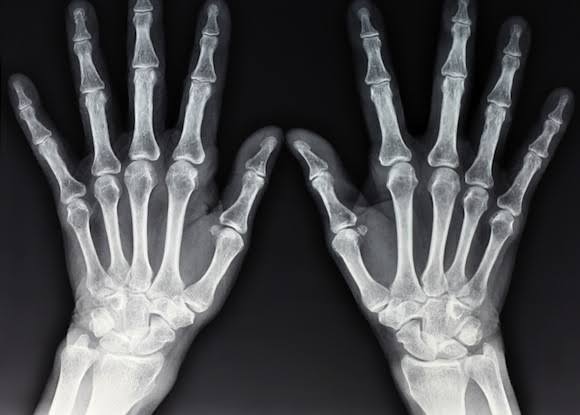

RAIO X: Saiba como o exame pode ajudar a detectar vários tipos de lesões

Através de um raio-x, pode ser feito o diagnóstico das várias lesões do sistema músculo-esquelético e geralmente são os primeiros exames solicitados na suspeita de uma lesão óssea, seja ela traumática (como fraturas, etc), degenerativas (osteoartrose), inflamatórias ou de causa reumatológica (artrites), tumorais, infecciosas, etc.⠀

As radiografias podem também diagnosticar, indiretamente ou parcialmente, alterações nos tendões, músculos e ligamentos e cartilagem articular.⠀

Estas estruturas podem sim apresentar alguma alteração detectável radiograficamente e, não raramante, estas alterações permitem um diagnóstico bastante preciso. Dessa forma, é necessário que o radiologista esteja atento a toda a área abrangida na radiografia, para não deixar passar nenhum detalhe e, portanto, nenhum diagnóstico.

Em caso de dor e/ou suspeita de uma determinada lesão no atleta, médicos do esporte e ortopedistas geralmente solicitam este exame. As radiografias podem ser úteis na avaliação de praticamente qualquer região do corpo: coluna vertebral, bacia, quadris, joelho, pé e tornozelo, ombro, cotovelo, etc, etc.